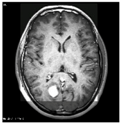

The system’s effectiveness is evaluated using the prescribed performance metrics, and the results are shown in Table 3. The introduced system efficiency is compared with deep convolution with a fully optimized framework (DC-FOF) [16], hybrid ensemble classifiers (HEC) [18], optimized radial basis function neural networks (RBFNN) [19], and multi-encoder net framework (MENF) [21]. The existing algorithm works effectively while recognizing the tumors. These methods utilize the hybridized function and segmentation procedures that minimize the computation complexity in the beginning stage. For these reasons, in this work, [16,18,19,21] are utilized for comparison purposes. The Confusion Matrix is a useful machine learning technique that measures recall, precision, accuracy, and the AUC-ROC curve. The ROC curve is utilized to evaluate a test’s total diagnostic performance and compare the performance of two or more diagnostic tests. It is utilized to choose optimal cut-off values for identifying the presence or absence of a brain tumor.

Table 3 also demonstrates that introduced region growing with fuzzy C-means clustering (RG-FCM) with the HHOCNN approach ensures high brain segmentation accuracy. The obtained results are maximum compared to the existing approach. Here, the RG-FCM with HHOCNN approach uses the seed points to select the cluster center. In addition, fuzzy membership functions are utilized to determine the exact center criteria. This process helps to reduce uncertainty issues while investigating the pixel regions effectively. Moreover, the CNN has different layers that also segment the region in the pre-training model. This process leads to minimizing the deviation between the actual and predicted values. Due to the effective analysis, the RG-FCM with HHOCNN approach attains 98%, as opposed to deep convolution with a fully optimized framework (DC-FOF) [16] (85.6%), hybrid ensemble classifiers (HEC) [18] (89%), optimized radial basis function neural networks (RBFNN) [19] (90.2%), and multi-encoder net framework (MENF) [21] (92.3%). According to the discussion, the graphical analysis of the introduced brain tumor identification process is illustrated in Figure 3.

Figure 3.

Segmentation Efficiency.

The network parameters are fine-tuned in every iteration using the value. The optimization process uses the coefficient vector and prey distance measure that helps to reduce the misclassification error rate and maximize the overall prediction accuracy.

The method uses the fully convolute layer functions to recognize the outputs (normal and abnormal). The network parameters are continuously regularized according to the whale prey searching procedure. The effective utilization of each function, objective function, and iteration helps retrieve the testing-related features more accurately. The obtained results are higher compared to the existing methods, such as deep convolution with a fully optimized framework (DC-FOF) [16], hybrid ensemble classifiers (HEC) [18], optimized radial basis function neural networks (RBFNN) [19], and multi-encoder net framework (MENF) [21] (see Table 3 and Figure 3).

The region growing with fuzzy C-means clustering (RG-FCM) with the HHOCNN approach attains maximum recognition accuracy. As stated, the computed output is compared with Equation (9) to compute the deviations. The deviation between the expected and predicted outputs is extremely low. If the computed values are minimum, it has been back propagated again to estimate the output value. During this process, the network performance is regularized by updating the network parameter values. The updating procedure uses the whale prey searching process. Here, the parameters are updated according to the value which improves the overall recognition accuracy. The obtained results exceed the performance of the existing reported approaches (see Table 3 and Figure 3).